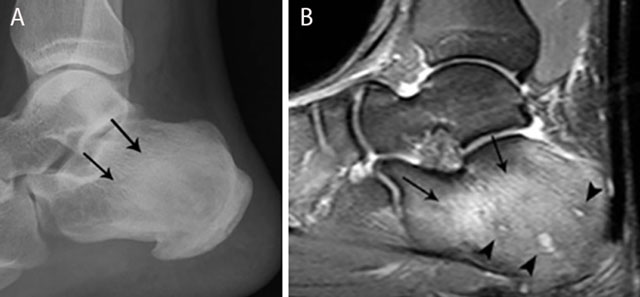

Figure 12

Chronic osteomyelitis of the calcaneus. Plain radiograph (a) and sagittal Fat–Sat T2–WI (b). Plain radiograph (a) shows inhomogeneous sclerosis (black arrows) in the calcaneus. Bone marrow edema (black arrows) is seen on MRI imaging (b), representing active infection. Note also the presence of small micro-abscesses (black arrowheads).

Inhomogeneous osteosclerosis and/or sequestrum formation (necrotic bone) is characteristic for chronic osteomyelitis on plain radiography. A sequestrum represents a segment of necrotic bone that is separated from the living bone by granulation tissue and bone resorption. It is typically denser than the living bone [13]. In some cases, a layer of new periosteal bone or involucrum is formed around the necrotic bone (Figures 7, 11, 12). On MRI, a sequestrum is hypo-intense on all pulse sequences. Gadolinium contrast administration may reveal a cloaca (opening in the involucrum) through which pus, granulation tissue and sequestra can be discharged. In addition, enhancement of sinus tracts tracking from the bone to the skin surface is well demonstrated on contrast enhanced MRI (Figure 13) [15].